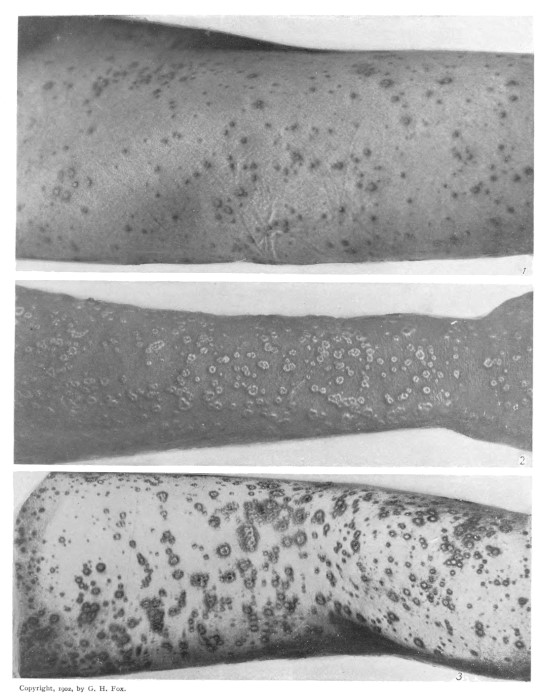

VI.

VARIOLA SEMI-CONFLUENS. (Fifth Day, Sixth Day.)

These illustrations show a partly confluent character which the eruption frequently presents, even in mild cases, and especially upon the legs. The influence of pressure in developing a more profuse eruption may be noted above the ankles, where shoes were laced, and below the knees, where garters were worn. [F.]